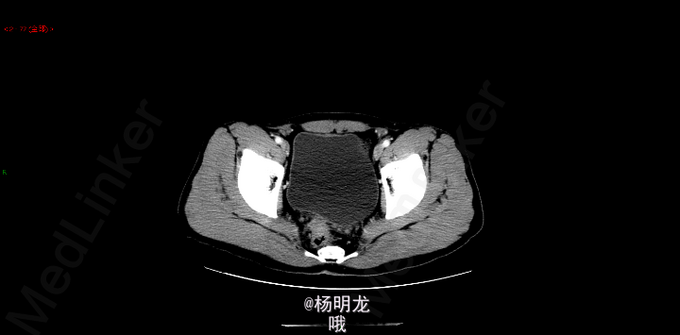

术前诊断 直肠癌 升结肠癌术后 双肺多发结节 转移瘤? 名称:开腹直肠癌切除,结肠造口术(Hartmann术) 探查:右上腹粘连,肝脏只探及部分,质地略韧,未触及肿物。直肠肿物上端位于盆底腹膜返折处,侵及腹膜,与左侧精囊粘连紧密。肿瘤4x4x3cm。无腹水,右腹部原术区未触及异常。 由于盆腔狭窄、粘连,向深部游离骶前间隙时出现静脉出血,紧急压迫止血。通过压迫不再出血后,于肿瘤上缘15 cm切断乙状结肠,于肿瘤下缘3cm以闭合器闭合直肠并切断直肠,切除肿瘤和肠管。 发生骶前静脉大出血,估计有2000ml。输血红细胞4u,血浆4u。

“结肠癌术后,化疗后” (1)(直肠切除标本) 直肠中-低分化腺癌,部分呈微乳头结构,伴少许黏液分泌,局部伴坏死,可见脉管瘤栓及神经侵犯。肿瘤细胞退变,伴纤维组织增生,符合中度治疗后改变(TRG3级),肿瘤侵透肌层累及直肠旁脂肪及盆底腹膜及环周切缘。上切缘及下切缘均未见癌。 淋巴结转移性癌(5/32) 肠壁淋巴结 5/15 肠系膜淋巴结 0/17 ypTNM分期:ypT3N2a 病例特点: 1.青年男性,双原发大肠癌; 2.升结肠癌(pTxN1bM1) 3.直肠癌(ypT4N2aMx),脉管瘤栓、神经侵犯,环周切缘受累。